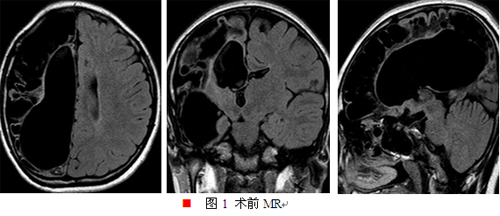

辅助检查:MR薄层扫描检查提示:1.右侧大脑半球及左侧额叶多发软化灶形成,并胶质增生、囊性脑萎缩;2.胼胝体发育不良;3.右侧内囊后肢、丘脑及大脑脚异常改变,考虑沃勒变性(如图一所示)。视频脑电图:异常脑电图III,间歇期:1.右半球半球生理节律减弱;2.癫痫样放电,①弥漫性,②右半球。发作期:BATS→过度运动,脑电图提示中线区著。fMRI:活动左侧肢体,右侧半球中央区未见激活,左侧半球SMA、中央前后回可见激活(如图二、三所示)。PET:右侧半球残存组织低代谢,左侧颞极及颞叶内侧结构低代谢(如图四所示)。IQ/MQ:全量表46,言语55,操作41,韦氏记忆<51。视野检查不配合。wada试验提示左侧为语言优势半球,左侧肢体运动功能已代偿转移到左侧大脑半球。